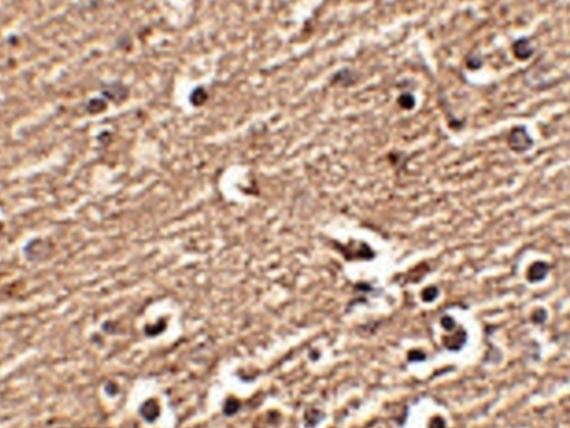

anti-SLITRK1 antibody for Western blot,IHC-Formalin-fixed paraffin-embedded sections and Human,Mouse,Rat

| 应用 | IHC-P, WB |

| 背景介绍 | This intronless gene encodes a member of the SLITRK protein family. These proteins are integral membrane proteins that are characterized by two N-terminal leucine-rich repeat (LRR) domains and a C-terminal region that shares homology with trk neurotrophin receptors. However, the protein encoded by this gene lacks the region of homology to neurotrophin receptors. The protein is thought to be involved in neurite outgrowth. Mutations in this gene may be associated with Tourette syndrome.[provided by RefSeq, Mar 2010] |